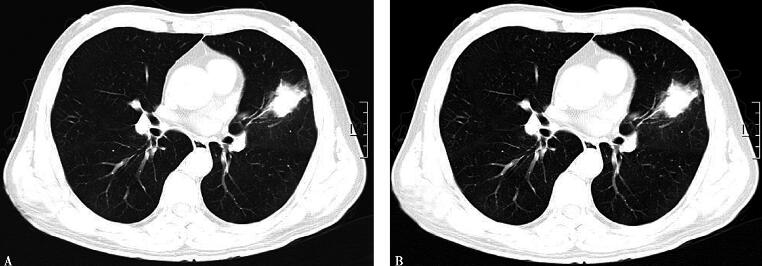

4.胸部CT:

左肺上叶舌段内见团块状密度增高影,周围有毛刺,呈支气管截断征,伴斑片状渗出影,纵隔内见淋巴结肿大(图1)。

图1

【临床分析】

重要的检查结果包括:

1.末梢血白细胞计数不高、中性粒细胞百分比升高。

2.胸部影像学提示左肺上叶见团块状高密度影,边缘有毛刺,呈支气管截断征,伴纵隔淋巴结肿大。其中最具有提示意义的就是影像学所见。结合其症状、体征及辅助检查结果,高度怀疑肺部恶性肿瘤伴纵隔淋巴结转移、阻塞性肺炎可能性大,可通过纤维支气管镜直接取病理以明确病变性质。